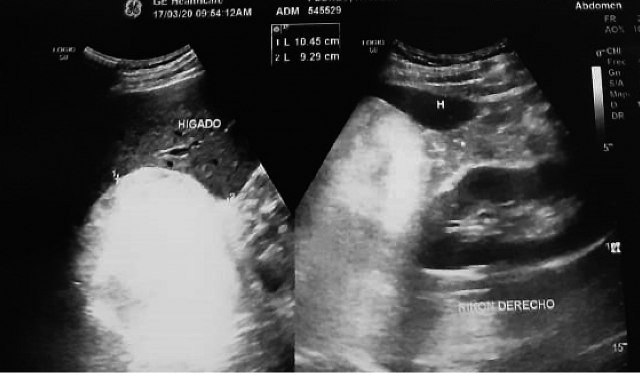

Presentamos el caso de un paciente masculino de 61 años de edad, con antecedente de hipertensión arterial sistémica de 6 años de diagnóstico, con adecuado control, quien acude a control por sintomatología urinaria obstructiva baja moderada, con dificultad para la micción, disminución de la fuerza y calibre de la micción, inició su padecimiento hace 1 año, por lo que se solicitan exámenes de laboratorio y gabinete de control, documentando, próstata de 80 gr, riñones normales, observando lesión sólida de 12 x 10 cm sobre el polo superior de riñón derecho, con escaso realce a la aplicación de Doppler, imagen hiperecoica con regiones hipoecoicas entremezcladas, sugestivas de mielolipoma suprarrenal ( figura 1).